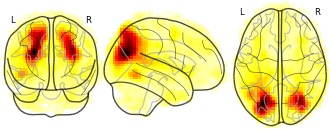

"description": "Multi-modal analysis in BPD. Brain regions exhibiting smaller gray matter and decreased activation during emotion processing in BPD compared to healthy controls. Note: Results were thresholded at p<.0025. Note2: Results were updated (see Erratum for this publication).",